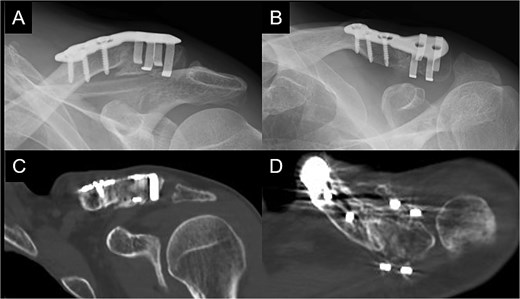

A 66-year-old man presented with left shoulder pain after falling. A Neer Type IIB fracture of the distal clavicle with significant displacement was revealed on radiographs (Fig. 1); however, owing to severe aortic valve stenosis and heart failure, the patient was deemed unfit for surgery. The patient underwent conservative treatment for distal clavicle fracture for 5 months; however, the pain in the left shoulder persisted, and significant skin protrusion caused by a displaced bone fragment was noted. No findings suggestive of neurovascular injury were observed. Radiography and computed tomography (CT) examinations revealed fracture displacement progression (Fig. 2A–C). After undergoing aortic valve replacement 3 months postinjury, the cardiac function of the patient improved and surgery was performed to treat the distal clavicle nonunion.

Radiographs (A and B) and CT scans (C and D) captured after 5 months of conservative treatment show that the displacement has progressed.